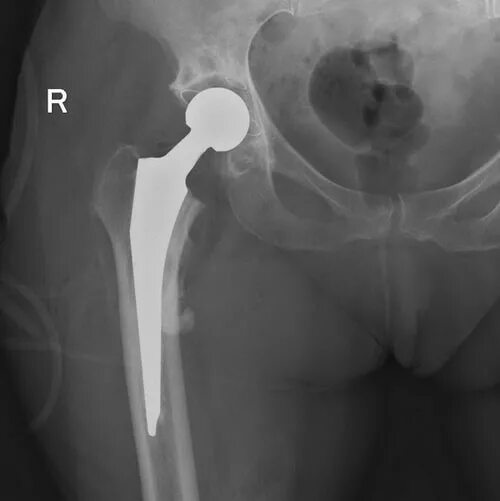

Упражнение тазобедренного сустава некроз